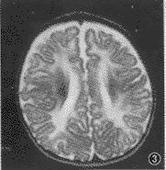

胼胝體進行性變性既往又稱作Marchliafara-Bignami病,是一種并發(fā)于慢性酒精中毒的罕見疾病。多為中年男性,常與營養(yǎng)不良和其他酒精性疾病共存。病變主要侵犯胼胝體中間層,其次為鄰近的大腦白質(zhì)和小腦中腳也可受累。無特異治療方法,預后不良。